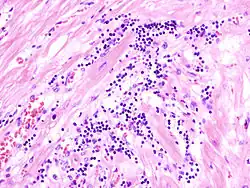

Virale Myokarditis

Pathogenese: Herzmuskelnekrose durch Virus und T-Zell-vermittelte Immunreaktion.

Mikro: Interstitielles lymphozytäres Infiltrat (kleine blaue Zellen), kaum Nekrosen.